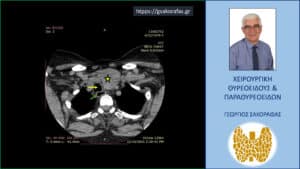

Αξονική τομογραφία – εγκάρσια διατομή σε ακόμη χαμηλότερο επίπεδο. Απεικονίζεται ο ευμεγέθης καταδυόμενος όζος (κίτρινος αστερίσκος) και η απώθηση προς τα δεξιά της τραχείας (κίτρινο βέλος) και του οισοφάγου (πράσινο βέλος).